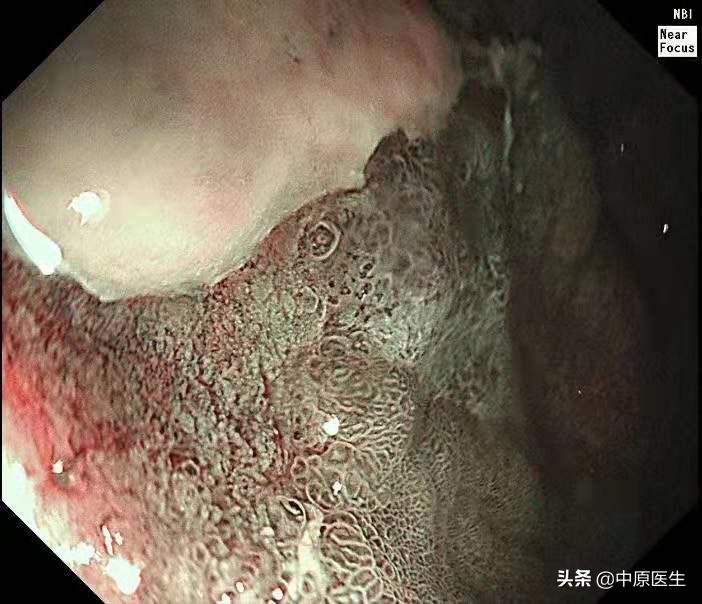

这个患者的溃疡多发,不算太大,并且表面的苔很干净,底部也算平坦,尤其是新发现的两个溃疡,从这几个条件来看,似乎良性可能性大。但是,我还是不放心。我现在只是用了白光检查,为什么不选择窄带光,放大检查?虽然麻烦一点,但是,可以看到更多细节!于是,我打开NBI模式,并且使用变焦(俗称放大,可以达到和显微镜下看类似的效果),再仔细地对每一处病变进行了观察,结果竟然发现,虽然范围很小,尤其是胃窦处的溃疡,不超过2个毫米的范围内我都发现了腺管缺失和血管异常扩张的地方,这往往提示病变有可能已经癌变,在放大镜的引导下,我对病变进行了精准活检。

周一上午,病理出来了,结果触目惊心,每一处溃疡都取到了癌组织,至此该患者诊断明确,他已经不是胃镜可以切除的早期胃癌,更不是良性的胃溃疡,而是需要进行外科手术切除的胃癌!